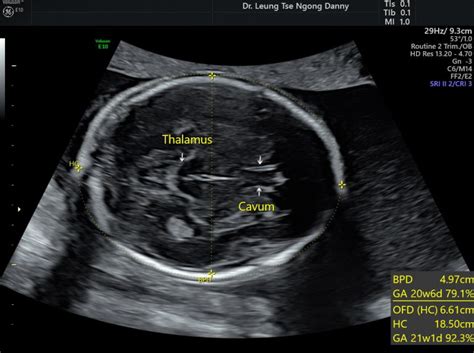

Understanding fetal biometry is crucial during pregnancy, especially around the 28-week mark. This article will delve into the normal ranges for various fetal measurements, including IPSE, IBP, DSE, HC (Head Circumference), AC (Abdominal Circumference), and FL (Femur Length). These measurements help healthcare providers assess your baby’s growth and development, ensuring everything is on track for a healthy delivery. So, let’s break down what each of these measurements means and what constitutes a normal range at 28 weeks. Knowing these ranges can provide reassurance and help you better understand your baby’s development during this important stage of pregnancy. It’s all about keeping an eye on those milestones and ensuring your little one is growing strong! Fetal biometry uses ultrasound to estimate the size and weight of the fetus during pregnancy. Measurements like biparietal diameter (BPD), head circumference (HC), abdominal circumference (AC), and femur length (FL) are taken and compared to standard growth curves for gestational age. This helps assess fetal growth, identify potential growth abnormalities, and estimate fetal weight. Regular monitoring of these biometric parameters is crucial for identifying potential issues early and ensuring appropriate management of the pregnancy. In the following sections, we’ll go into more detail about each specific measurement, explaining how they’re obtained and what their normal ranges are. This information should provide a comprehensive overview of fetal biometry and its importance in prenatal care.

Head Circumference (HC) is a vital measurement in fetal biometry, providing insights into the baby’s brain growth. At 28 weeks, the normal range for HC typically falls between 25.3 cm and 28.3 cm. This measurement is obtained by carefully tracing the outline of the baby’s head on an ultrasound image. It’s important to remember that these are just average ranges, and slight variations can occur depending on individual factors. Factors influencing HC include genetics, maternal health, and overall fetal growth patterns. If the HC measurement falls outside the typical range, your healthcare provider will investigate further to determine if there’s any cause for concern. This might involve additional ultrasounds or other tests to assess the baby’s development more comprehensively. It’s crucial to maintain regular prenatal checkups so your doctor can monitor these measurements and address any potential issues promptly. Remember, early detection and intervention can make a big difference in ensuring a healthy outcome for your baby. So, keep those appointments and don’t hesitate to voice any concerns you might have. Your healthcare team is there to support you every step of the way. Keeping track of head circumference helps doctors monitor brain development. Significant deviations from the normal range can indicate potential problems, such as microcephaly (smaller than normal head size) or macrocephaly (larger than normal head size). Regular monitoring and appropriate interventions are crucial for addressing any concerns and ensuring the best possible outcome for the baby’s neurological development. So, head circumference measurement is an important tool for monitoring fetal health.